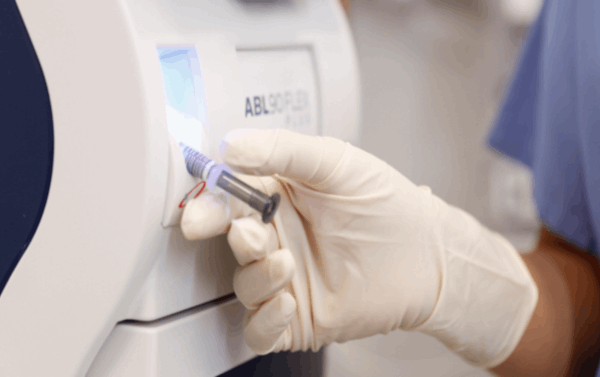

La gasometría arterial es una técnica médica fundamental que se utiliza para analizar el equilibrio ácido-base y evaluar la función respiratoria en pacientes. Consiste en la extracción de una muestra…